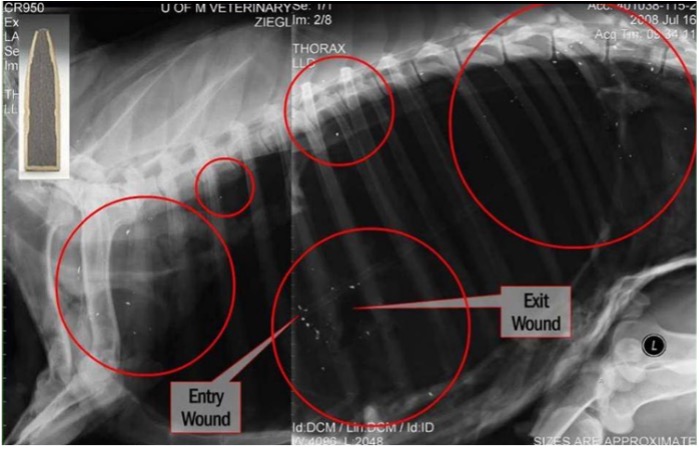

When an animal is shot with common lead bullets, as much as a third or more of the bullet's total weight can be fragmented into hundreds of tiny pieces upon impact and remain inside as much as 18 inches from the pathway of the bullet. Lead bullets can fragment even if it passes all the way through the intended target without hitting bones or major organs. Some of these lead fragments are so small they are not visible to the naked eye but are clearly present in x-rays.

When gut piles or parts of animal carcasses remain or are placed in the field, including when they are used for bait, lead fragments often are left with it. Avian scavengers take advantage of these free meals, ingesting lead fragments while consuming the meat. When they do, the lead toxifies their blood, tissue and bones, causing neurological and motor impairments that can lead to death within a matter of days.